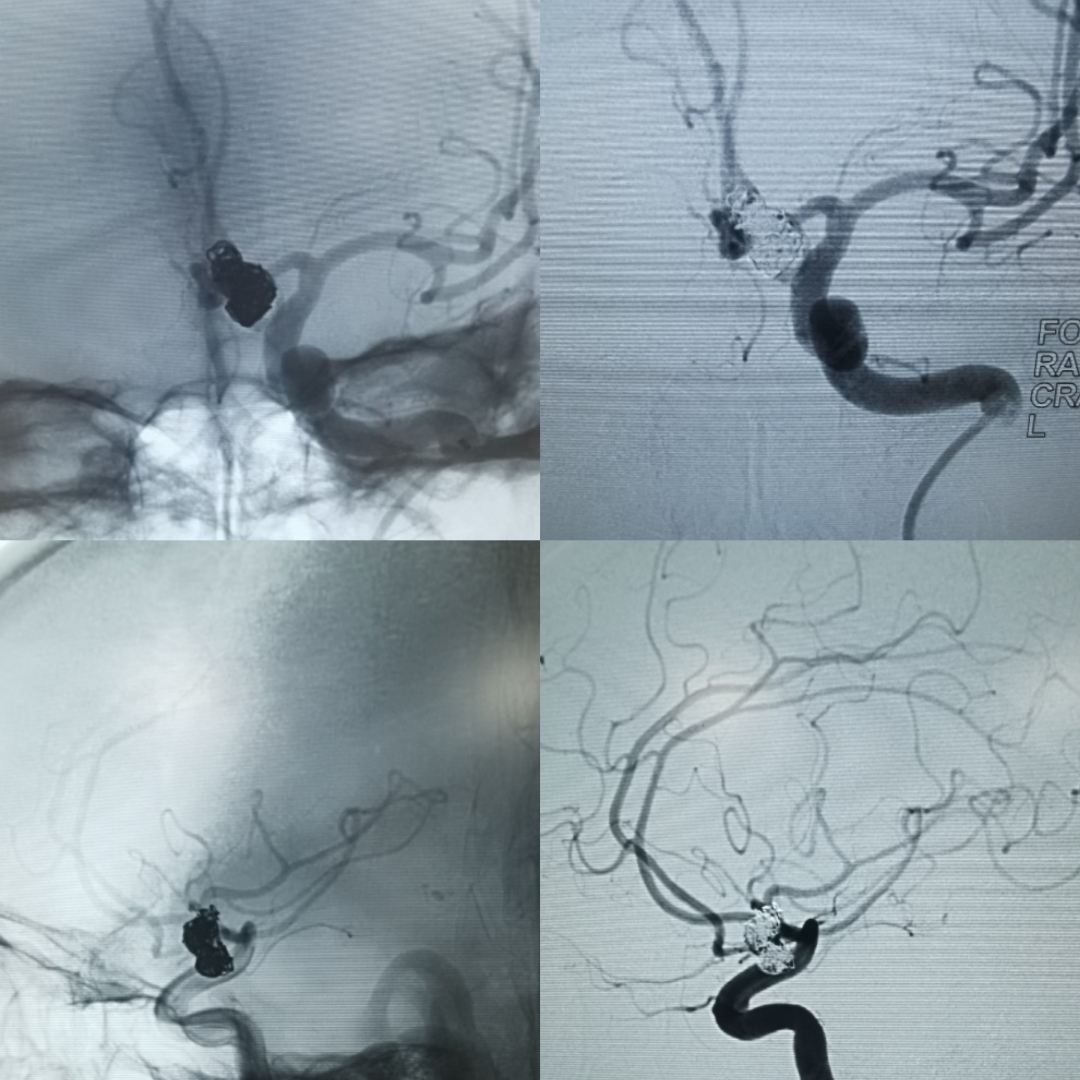

采用双微导管技术,其中一根为导管头端塑成S形,指向瘤体的上部,另外一根微导管塑成C形,指向瘤体的下端,同时,两根味道管经过留颈部,可以起到对瘤颈以及双侧A2的部分保护作用。弹簧圈填塞过程中应反复造影,确保双测A2血流通畅。

术后三维旋转造影可以看到动脉瘤不显影,双侧A2血流通畅,达到预期手术效果。